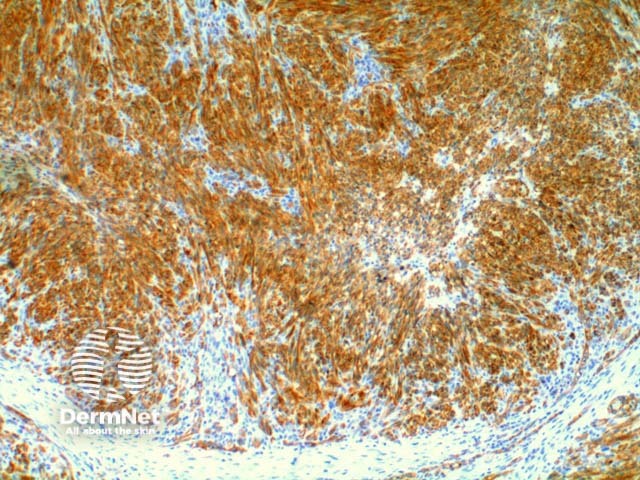

Lesional cells in Kaposi sarcoma are positive to the non-specific endothelial markers CD31 (Figure 7) and CD34, and also to the lymphatic endothelial marker D2-40 or podoplanin. The antibody to HHV-8 (Human Herpes Virus 8) latent nuclear antigen 1 is a highly specific commercial stain and has simplified the diagnosis in difficult cases. Figure 8.

Figure 7